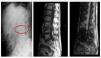

A 63-year-old-male with a history of long-standing DM, liver disease due to hepatitis C virus, pulmonary tuberculosis, peripheral arterial disease and stage V CKD on haemodialysis, who received renal transplant with recurrence of renal dysfunction, restarting haemodialysis with IJC. He came to the Emergency department following 5 days of severe lower back pain with apparently mechanical characteristics associated with fever of 38°C on occasions. The analysis emphasised high leukocytosis with left shift, C-reactive protein of 12.9 and procalcitonin of >10. A bone scintigraphy was performed, where increased uptake foci were not observed, suggesting infectious-inflammatory process. However, the MRI showed images compatible with L3-L4 SD with paravertebral abscess (Figure 1). Blood cultures were positive for vancomycin-sensitive Staphylococcus epidermidis, linezolid and co-trimoxazole. The use of lumbar corset, analgesic treatment with fentanyl patches and antibiotic coverage are prescribed, initially with intravenous vancomycin in dialysis for 3 months, which was changed to daptomycin due to persistent clinical symptoms. After nearly 6 months of treatment, significant clinical improvement, negative blood cultures and near normalisation of acute phase reactants was achieved. The patient remains on haemodialysis without any other significant complication.

Figure 1. Radiology and MRI